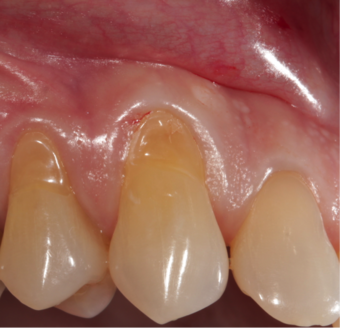

Abrasion is the non-carious, mechanical wear of tooth from interaction with objects other than tooth-tooth contact.[1] It most commonly affects the premolars and canines, usually along the cervical margins.[2] Based on clinical surveys, studies have shown that abrasion is the most common but not the sole aetiological factor for development of non-carious cervical lesions (NCCL) and is most frequently caused by incorrect toothbrushing technique.[3]

Abrasion frequently presents at the cemento-enamel junction and can be caused by many contributing factors, all with the ability to affect the tooth surface in varying degrees.[4]

The appearance may vary depending on the cause of abrasion, however most commonly presents in a V-shaped caused by excessive lateral pressure whilst tooth-brushing. The surface is shiny rather than carious, and sometimes the ridge is deep enough to see the pulp chamber within the tooth itself.